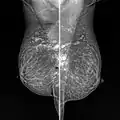

Snowball like hyperechogenic axillary lymph nodes in a woman with silicone implants removed due to complications